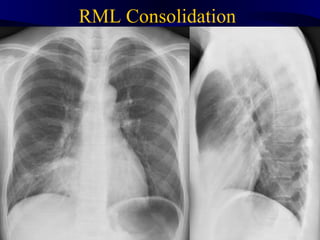

RML Consolidation Rmlconsolidation